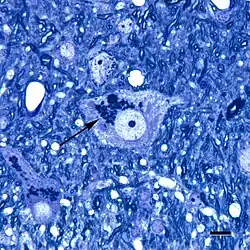

Micrograph showing a cluster of lipofuscin particles (arrow) in a nerve cell of the brain; toluidine blue stain; scale bar = 10 microns (0.01 millimeters)